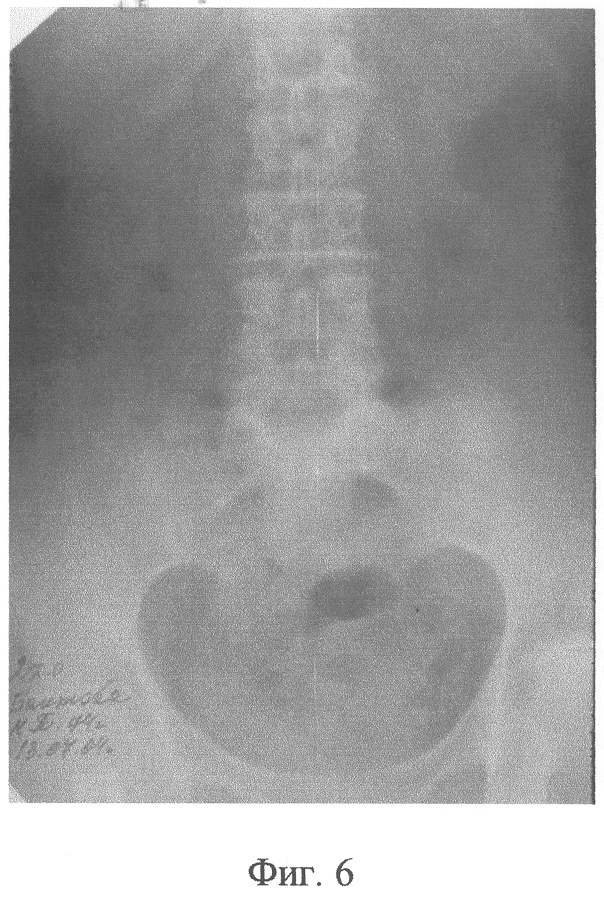

Фиг.6 – рентгенограмма больной Б., 10 сутки после операции, произошло отхождение компрессионных устройств;

На 10 сутки после операции компрессионные устройства из зоны образованного анастомоза самостоятельно отторглись и эвакуировались естественным путем, в результате чего сформировалось полноценное соустье (Фиг.6). Колостому на передней брюшной стенке через 16 суток закрыли внебрюшинным способом. После этого, на 9 сутки, больная выписана с хорошей функцией анастомоза (Фиг.7, 8).